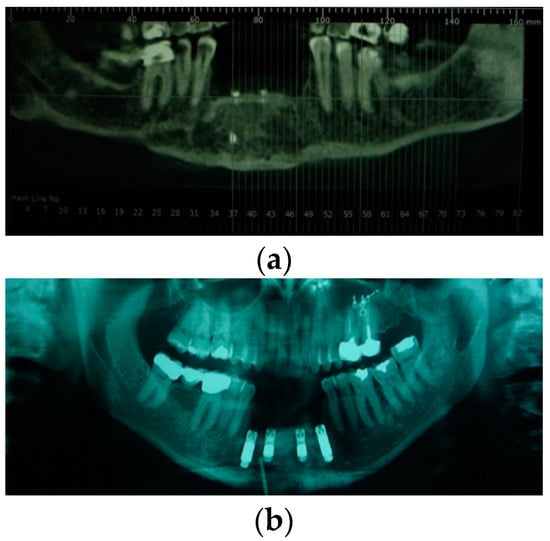

Figure 5.

(a)CT scan before reconstruction surgery and prosthetic rehabilitation; (b) 3D CT scan after reconstruction surgery with osteomyocutaneous free fibula flap; (c) CT scan after placement of six implants.

In the second case, a high-velocity ballistic trauma caused the destruction of right premaxilla and the loss of dental elements 1.1, 1.2, 1.3, 1.4, 1.5, and 2.1 and adjacent soft tissue. The patient presented an extensive hard and soft tissue disruption; he lost a large portion of labial soft tissue, and he showed a retracting and hypertrophic scar in the traumatized zone. The first surgery was performed: it consisted of a right emimaxillectomy followed by the second reconstructive surgery with osteomyocutaneous free fibula flap. Four months after definitive surgery and reconstruction, the implant surgery was performed, and six implants, namely “Zimmer Trabecular Metal”, were inserted in right emimaxilla. In a second step, the reconstruction of the upper lip using an Abbé mucocutaneous flap was performed. After four months, we inserted healing screws, and six months later, the patient finalized treatment (Figure 4, Figure 5 and Figure 6).